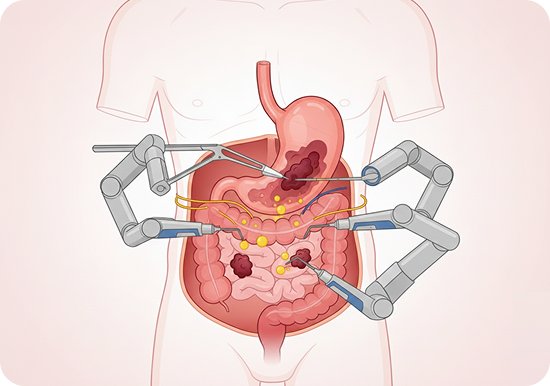

Gastrointestinal Oncology

- Surgery for stomach and colorectal cancers

- HIPEC (Hyperthermic Intraperitoneal Chemotherapy) for advanced GI cancers

- Minimally invasive and robotic-assisted pancreatic surgery

- Laparoscopic and robotic-assisted gastrointestinal surgeries